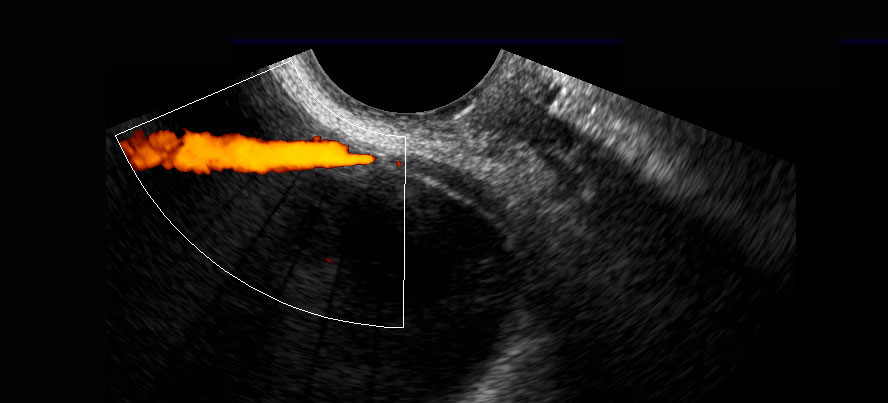

Ở người phụ nữ này, đoạn niệu quản xa bình thường (đầu mũi tên) đã được hiển thị, bao gồm cả “hiện tượng tia phụt” của niệu quản khi sử dụng Doppler. Lưu ý khoảng cách nhỏ giữa đầu dò âm đạo và niệu quản đoạn xa.